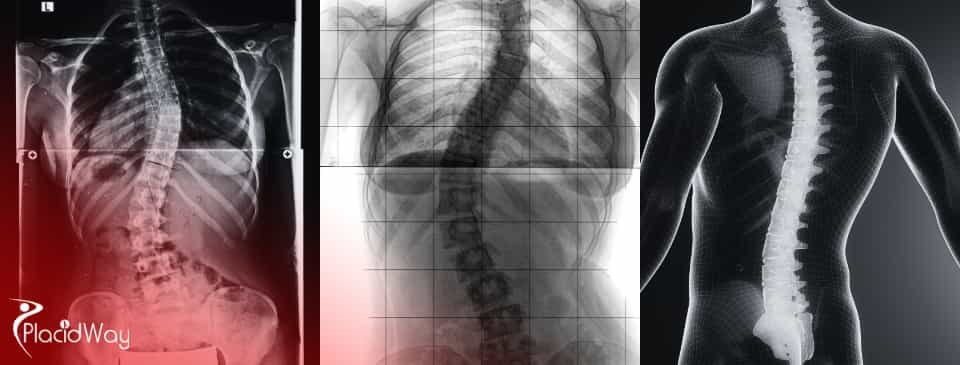

Scoliosis is an abnormal sideways curvature of the spine, which can present as a C-shape or S-shape, often accompanied by spinal rotation. It can affect children, adolescents, and adults, leading to pain, deformity, and, in severe cases, impacting lung function.

Scoliosis is more than just a crooked spine; it's a complex spinal deformity where the spine curves abnormally to the side, often rotating at the same time. While a slight curve might be harmless, significant curvatures can lead to noticeable postural imbalances, discomfort, and in severe instances, compromise the function of internal organs like the lungs. There are several types of scoliosis: